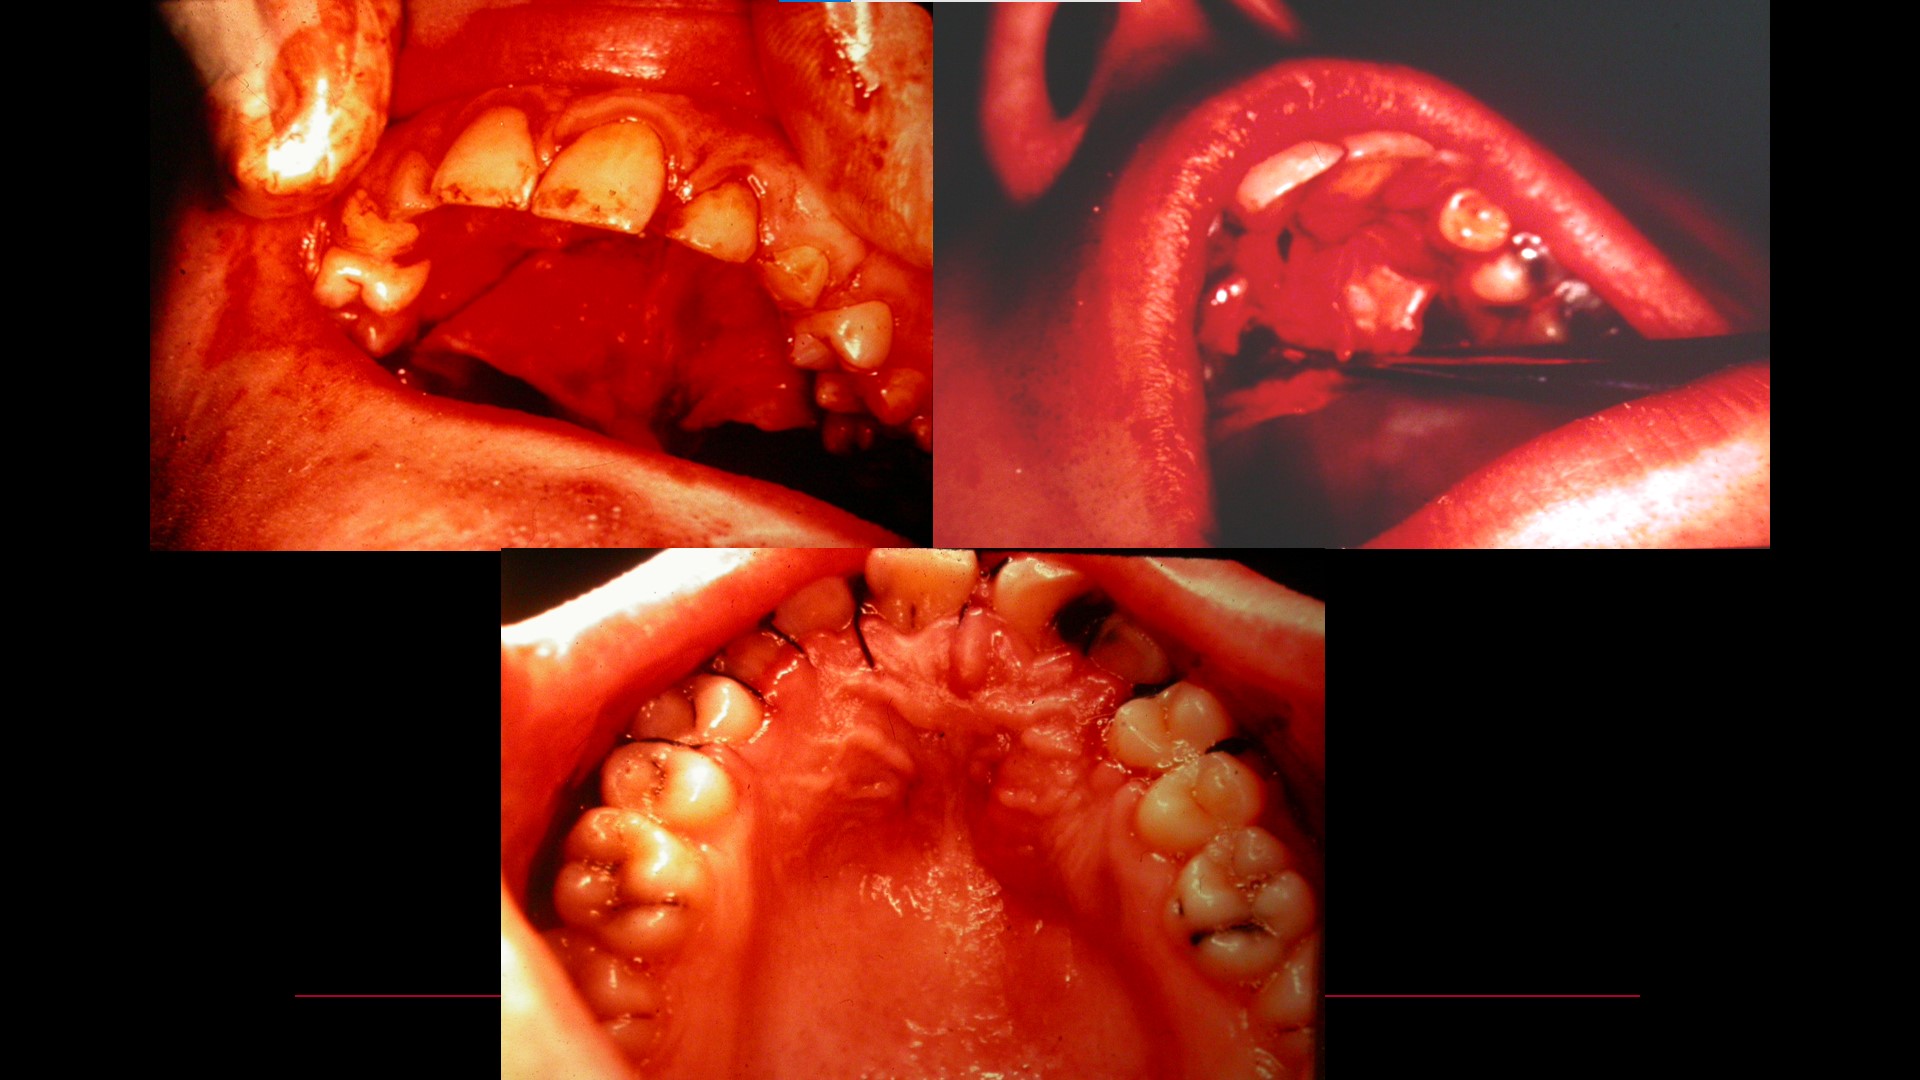

Impacted teeth

Oral Surgical Procedures